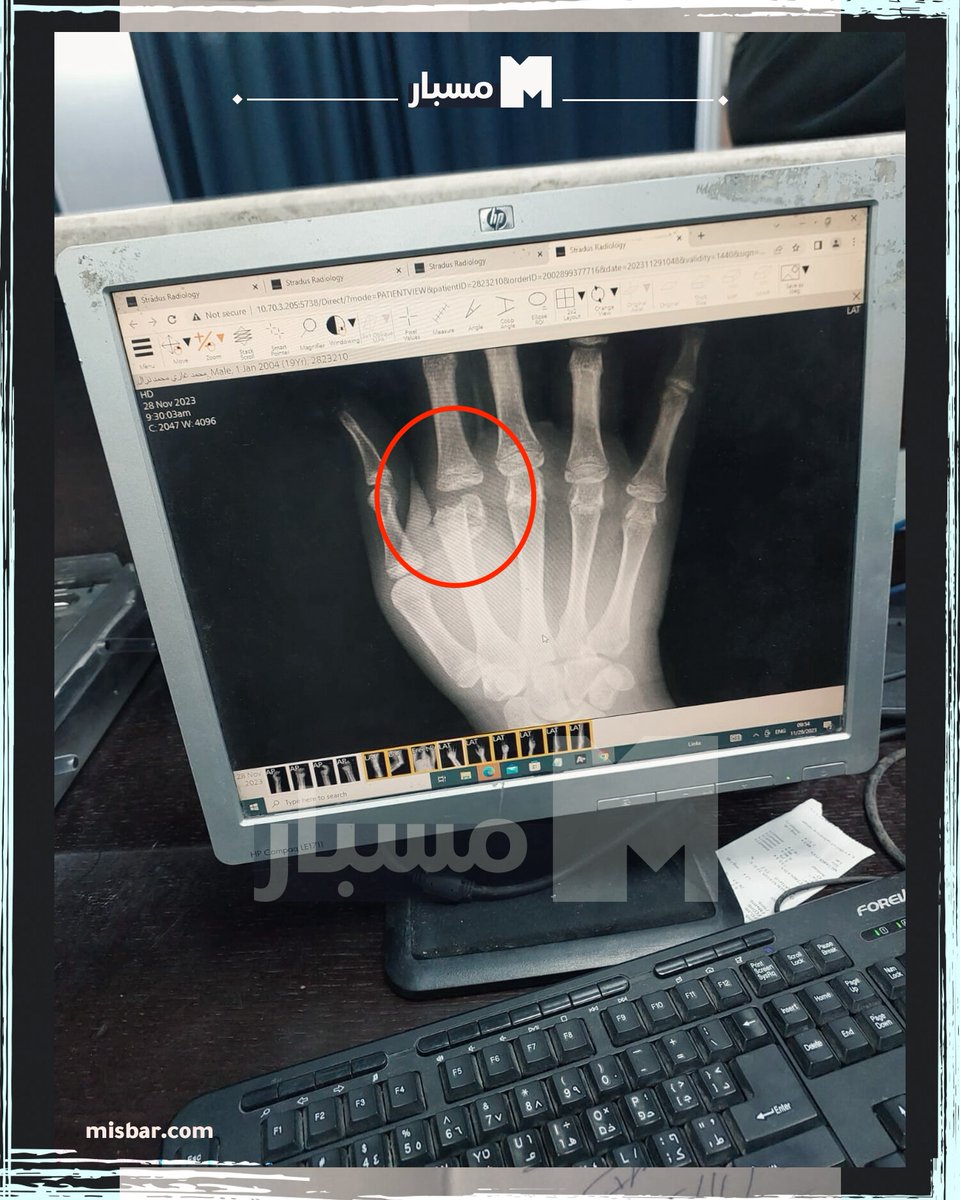

5\ UPDATE: Mohammed Nazal's medial record was just released: showing broken & fractured fingers, contusions in his arms & bruises on his back. The report recommends "surgical fixation" to correct the fingers that were broken & left for days without treatment.

The report recommends "surgical fixation" to correct the fingers that were broken & left for days without treatment.